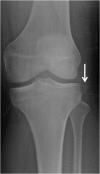

Emergency and trauma care produces a "perfect storm" for radiological errors: uncooperative patients, inadequate histories, time-critical decisions, concurrent tasks and often junior personnel working after hours in busy emergency departments. The main cause of diagnostic errors in the emergency department is the failure to correctly interpret radiographs, and the majority of diagnoses missed on radiographs are fractures. Missed diagnoses potentially have important consequences for patients, clinicians and radiologists. Radiologists play a pivotal role in the diagnostic assessment of polytrauma patients and of patients with non-traumatic craniothoracoabdominal emergencies, and key elements to reduce errors in the emergency setting are knowledge, experience and the correct application of imaging protocols. This article aims to highlight the definition and classification of errors in radiology, the causes of errors in emergency radiology and the spectrum of diagnostic errors in radiography, ultrasonography and CT in the emergency setting.